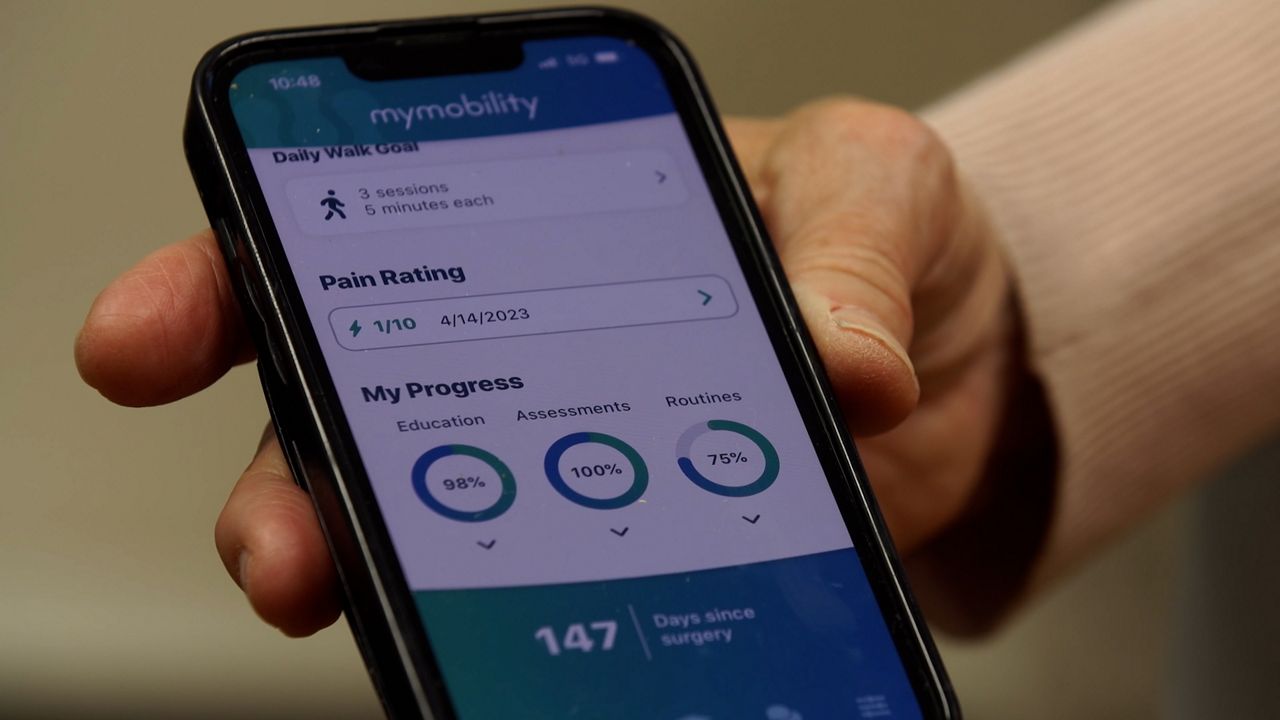

The implants wirelessly transmit data to clinicians on the range of motion, step count, walking speed and other gait metrics. Patients can also download an app that offers insights into how to recover better.